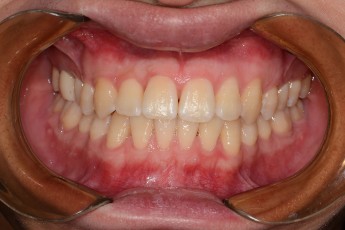

Before

After